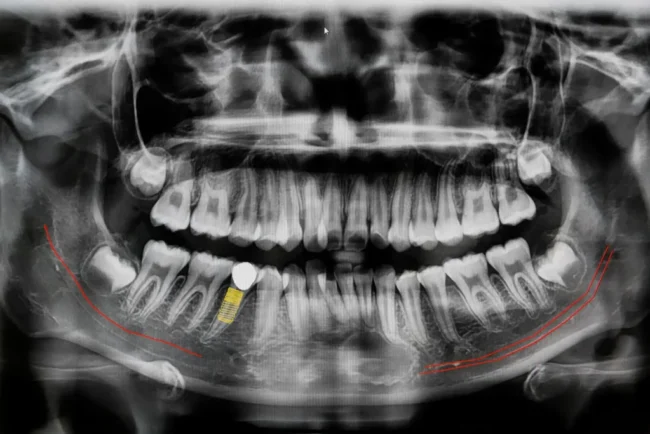

Un sorriso allineato non è soltanto una questione estetica: è anche sinonimo di salute, equilibrio e benessere. L’ortodonzia fissa è una delle soluzioni più affidabili per correggere i disallineamenti dentali e migliorare la funzionalità della bocca, restituendo ai pazienti un sorriso armonioso e una masticazione corretta. Cos’è e come funziona l’ortodonzia fissa L’ortodonzia fissa utilizza un…